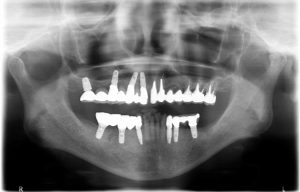

まずはレントゲン写真から

4年前に来院した時には右上、左下のブリッジが脱落し根は残せない状態でした。その後インプラント治療を選択、無事完了。

次に来院された時は右下のブリッジが脱落し、またしても根は残せない状態になっていました。

再度右下3本と、左下1本インプラントを入れて無事治療は終了しました。